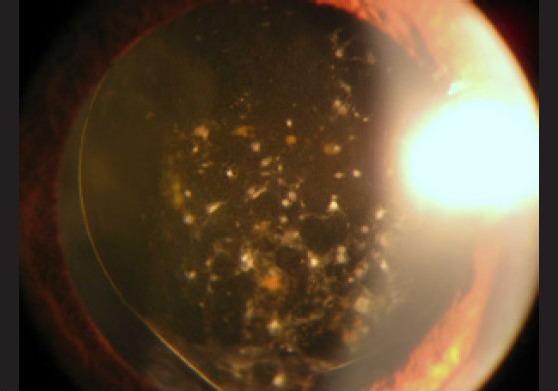

Surgery in the management of uveitis can be divided based on indication: either for therapeutic or can be for diagnostic purposes or to manage complications. The commonest indications include: Visual rehabilitation: surgery for removal of cataract, band keratopathy, corneal scars, pupillary membranes, removal of dense vitreous membranes, management of complications: anti-glaucoma surgery, vitreous hemorrhage, retinal detachment and chronic hypotony and diagnostic: aqueous tap, vitreous biopsy, tissue biopsy (iris, choroid). In this review, we shall describe the surgical technique for visual rehabilitation and for management of complications.

手术的目的可以是治疗性的,也可以是诊断性的,或者是为了处理并发症。最常见的适应证包括:视力康复:手术去除白内障、带状角膜病变、角膜瘢痕、瞳孔膜、去除致密玻璃体膜、处理并发症:抗青光眼手术、玻璃体积血、视网膜脱离和慢性低眼压以及诊断性手术:房水穿刺、玻璃体活检、组织活检(虹膜、脉络膜)。在本篇综述中,我们将描述用于视力康复和处理并发症的手术技术。